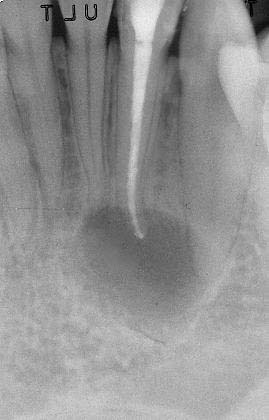

Apertura della corona fino ad arrivare alla camera pulpare (tale trattamento viene eseguito tramite anestesia locale). Si rimuove la polpa e si cercano i canali radicolari del dente, una volta trovati si estirpano i nervi. Si allargano e si puliscono i canali del dente, (tramite strumenti al Nichel titanio o strumenti manuali) prendendo anticipatamente le misure dei canali (per non uscire oltre apice). Si disinfettano i canali e si eseguono vari lavaggi tra un passaggio e un altro per elimininare il fango dentinale. Il medico a questo punto verifica la possibilità di chiudere definivamente i canali o lasciare il dente in prova, inserirendo nei canali un disinfettante e eseguendo una chiusura provvisoria. Al momento di chiudere il dente definivamente, questo viene preparato rieseguendo le misure dei canali da chiudere ed usando per la stessa lunghezza del canale, un cono di guttaperga del diametro necessario. Si scalda il cono in guttaperga e si inserisce nel canale. Durante il trattamento endodondico vengono effettuati una serie di esami radiografici per verificare i risultati, le lunghezze, la forma dei canali.

L'esame radiografico, fondamentale per porre diagnosi in odontoiatria, in endodonzia è irrinunciabile perché è l'unico strumento che ci permette di "vedere" all'interno della radice del dente, è quindi molto importante la possibilità di effettuare lastre con apparecchiature digitali che emettono un quarto della dose di raggi emessa da un radiografico tradizionale e che permettono di conservare la radiografia endorale in una cartella informatica del paziente senza possibili alterazioni nel tempo.